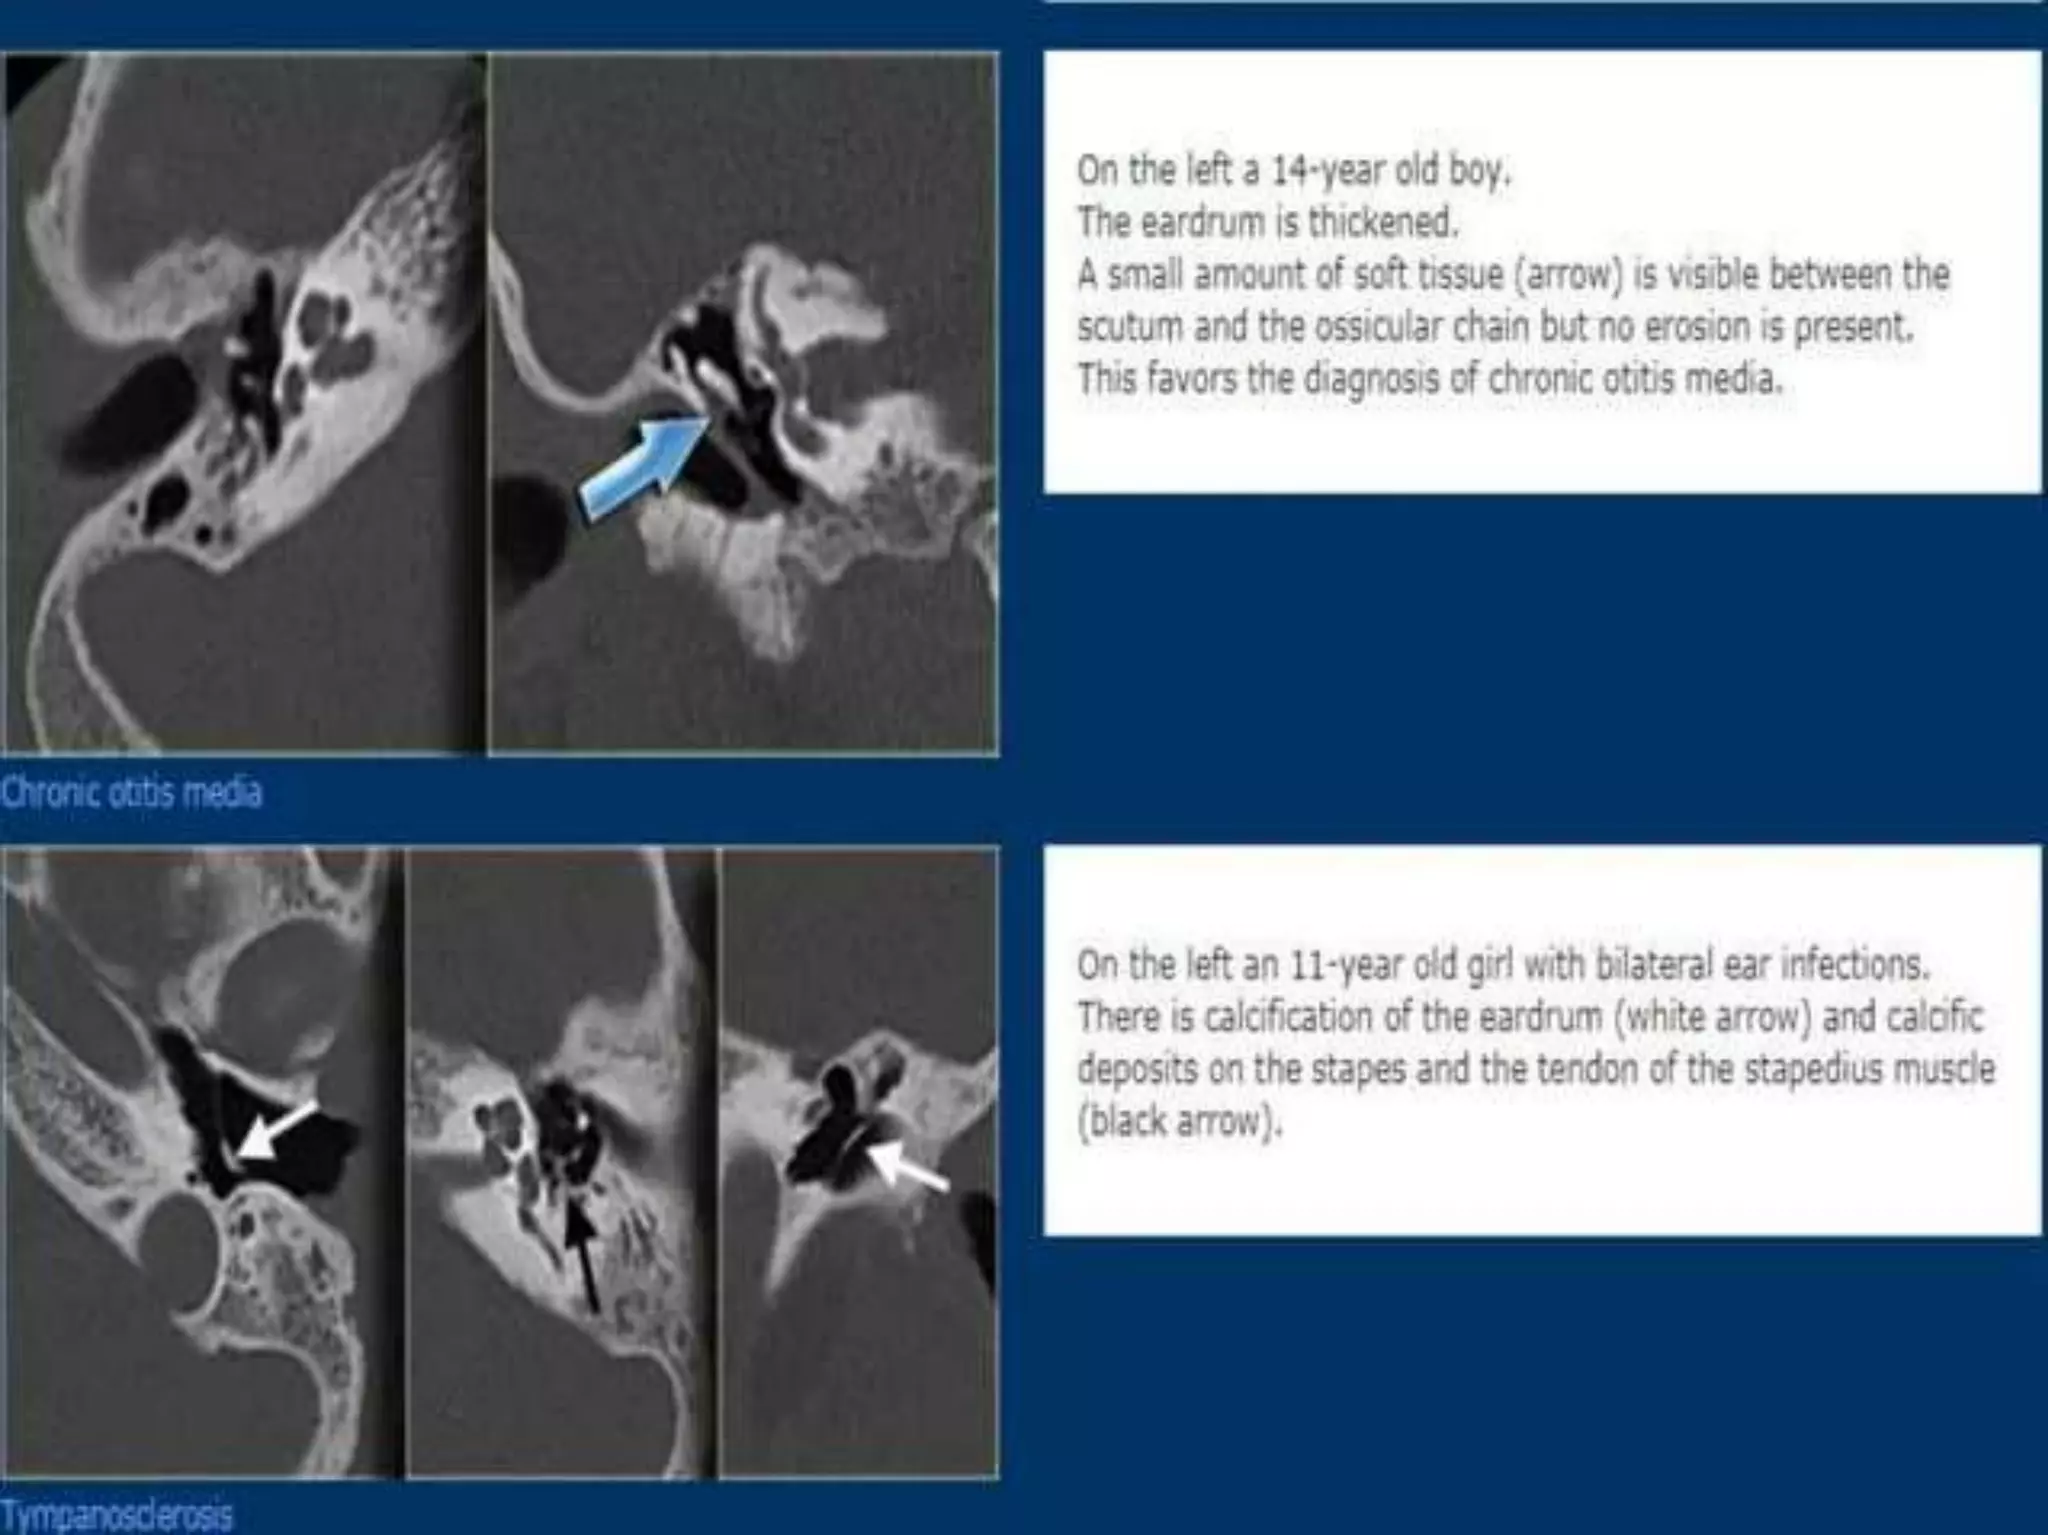

Chronic otitis media is a chronic inflammation of the middle ear and mastoid cavity that presents with recurrent ear discharge through a perforated eardrum. It has several subtypes depending on the state of the eardrum perforation and epithelium. It can be caused by prior acute otitis media, genetics, environment, eustachian tube issues, gastroesophageal reflux disease, craniofacial abnormalities, or immune deficiency.